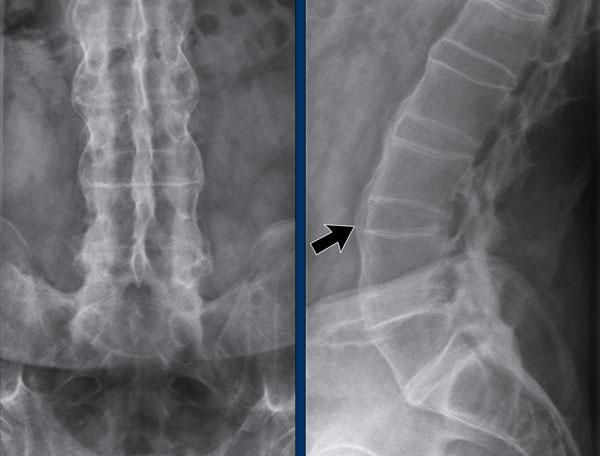

Cột sống tre

Hình ảnh cột sống tre trong viêm cột sống dính khớp.

Hợp nhất cột sống thắt lưng do gai xương syndesmophyte và vôi hóa dây chằng cạnh sống.

Lưu ý vôi hóa dây chằng (mũi tên).

Cột sống tre cứng đờ dễ bị gãy do cơ chế ưỡn quá mức, ngay cả sau chấn thương nhẹ.

Luôn cần nghi ngờ cao về các gãy xương này ở bệnh nhân có cột sống cứng!

Cột sống tre thường bắt đầu ở đoạn thắt lưng và có thể lan lên đến cột sống cổ.

Lưu ý hình vuông hóa thân đốt sống (mũi tên).